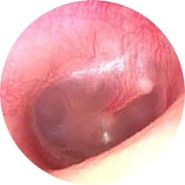

| LEVEL | DESCRIPTION | PICTURE |

| TEED 0 | Normal tympanic membrane. No evidence of injury despite the presence of symptoms. |

|

| TEED 1 | Diffuse redness and retraction of tympanic membrane. Erythema over part of the tympanic membrane due to inflammation, particularly around the manubrium. |

| TEED 2 | Diffuse redness and retraction of tympanic membrane, plus slight hemorrhage within the tympanic membrane. |

| TEED 3 | Diffuse redness and retraction of tympanic membrane, plus gross hemorrhage within the tympanic membrane. |

| TEED 4 | Dark and slightly bulging tympanic membrane due to free blood in the middle ear (a fluid level may also be present). |